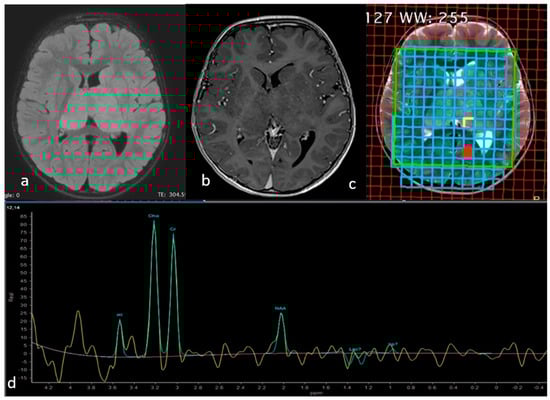

Twenty months later the child started to experience intentional and resting tremor affecting mainly the upper right limb. A brain and spinal MRI showed a bithalamic bicaudate signal abnormality suggestive of malignancy (Figure 2a,b). Multidisciplinary team discussion recommended surgical biopsy in order to obtain histological and immunohistochemical subtyping. The stereotactic biopsy target was identified on the MRI spectroscopy at the level of the inferior portion of the left thalamus, as this was the site of choline peak with low M-acetylaspartate level, expected to have greater tumor activity (Figure 2c,d).

Figure 2.

Axial FLAIR (a), Gadolinium-enhanced T1-weighted (b) and T2-weighted (c) MR images showing the lesion involving both thalami and head of caudate nuclei with no evident contrast enhancement. The spectrum (d) at the level of the yellow square in the left pulvinar corresponded to the area of highest cholin peak, where NAA was markedly decreased, chosen as the biopsy target.